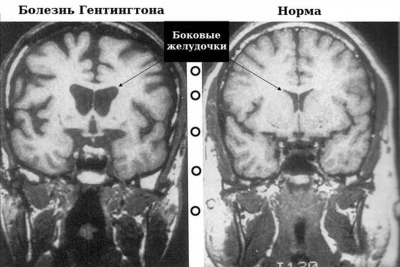

Ученые и медики заявили, что смогли в 4 раза замедлить развитие болезни Хантингтона

Базирующаяся в США и Нидерландах компания UniQure отчиталась о результатах нового метода лечения генетической н ...